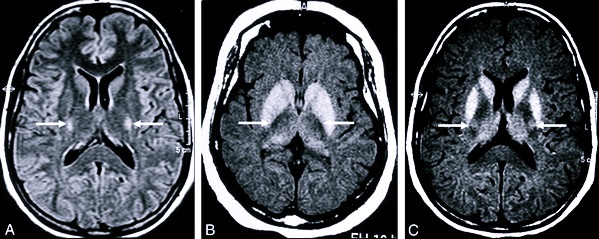

- магнитно-резонансную томографию;

Также проводится игольчатая ЭМГ, которая указывает на поражение мышц и их атрофию. МРТ необходима для уточнения диагноза, по ней можно проследить атрофию моторной коры головного мозга, дегенерацию путей, которые связывают центральные и периферические нейроны.